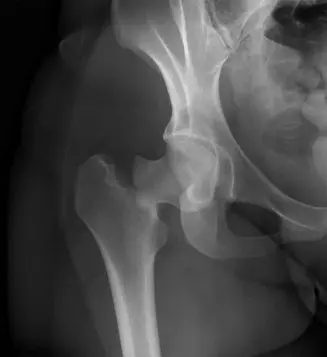

الأشعة السينية Plain Radiographs

يتم الحصول على صور بالأشعة السينية للحوض بالمنظر الأمامي الخلفي (AP Pelvis) وصورة جانبية مخصصة للورك المصاب (Cross-table Lateral Hip).

- نتائج الأشعة السينية في دراسة الحالة:

- صورة الحوض الأمامية الخلفية (AP Pelvis): أظهرت كسرًا داخل المحفظة المفصلية لعنق الفخذ الأيمن مع إزاحة. كان خط الكسر مائلًا، ويمتد من المنطقة تحت الرأسية إلى الأسفل والوسط. كان رأس الفخذ في وضعية إزاحة للخارج (valgus) بالنسبة لجذع الفخذ، وكان هناك حوالي 1 سم من الإزاحة العلوية لجذع الفخذ بالنسبة للرأس. بدا المدور الكبير سليمًا.

- صورة الورك الجانبية (Cross-table Lateral Hip): أكدت الإزاحة وقدمت رؤية أوضح لشكل الكسر، مبينة وجود تفتت خلفي كبير وامتداد للكسر إلى منطقة قاعدة العنق (basicervical region).

توضح هذه الصورة كسرًا في عنق الفخذ من النوع الثالث حسب تصنيف جاردن، مع انحشار وإزاحة للخارج.